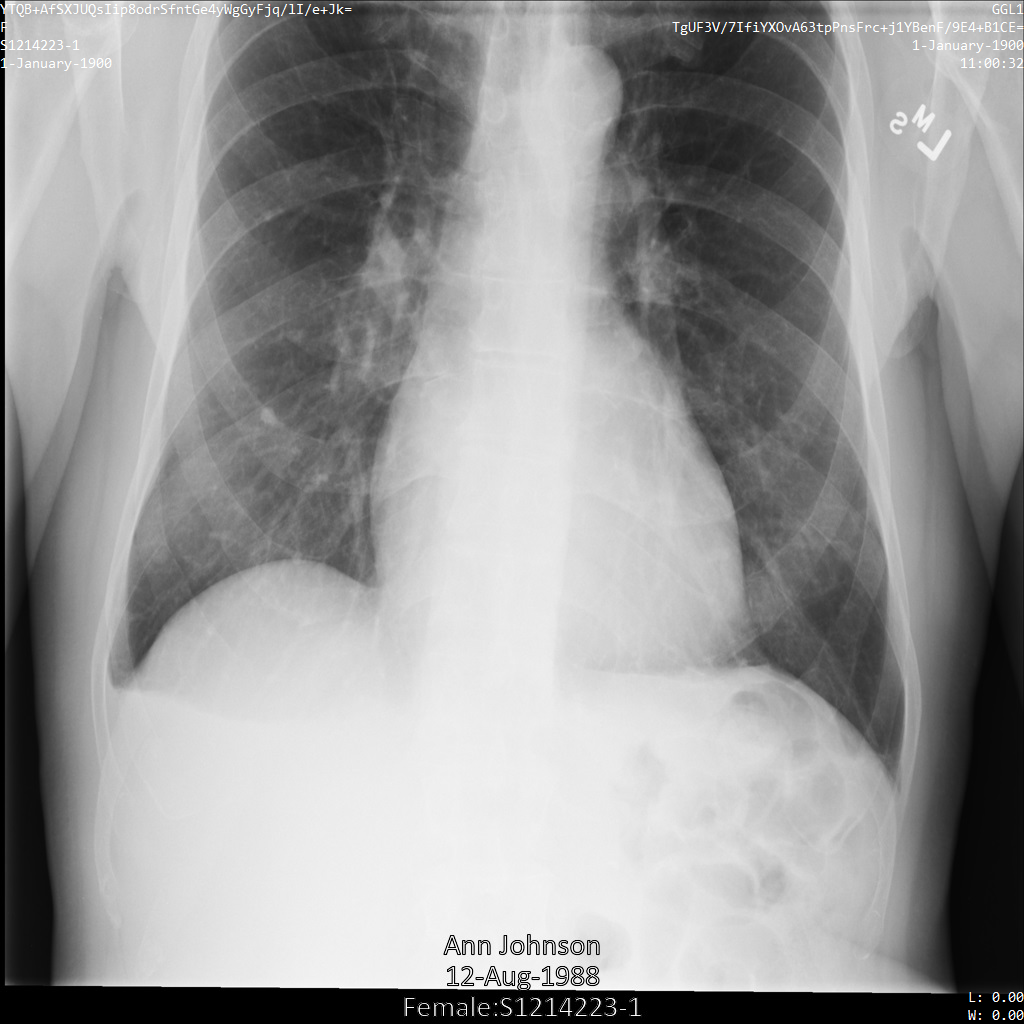

En la siguiente imagen, se muestra una radiografía sin ocultamiento de un paciente:

Después de enviar la imagen a la API de Cloud Healthcare mediante la opción REDACT_SENSITIVE_TEXT, la imagen aparece de la siguiente manera:

Puedes ver que ocurrió lo siguiente:

- Se ocultó el elemento

PERSON_NAMEen la esquina inferior izquierda de la imagen - Se ocultó el elemento

DATEen la esquina inferior izquierda de la imagen

El sexo del paciente no se ocultó porque no se considera texto sensible de acuerdo con los Infotipos de DICOM predeterminados.